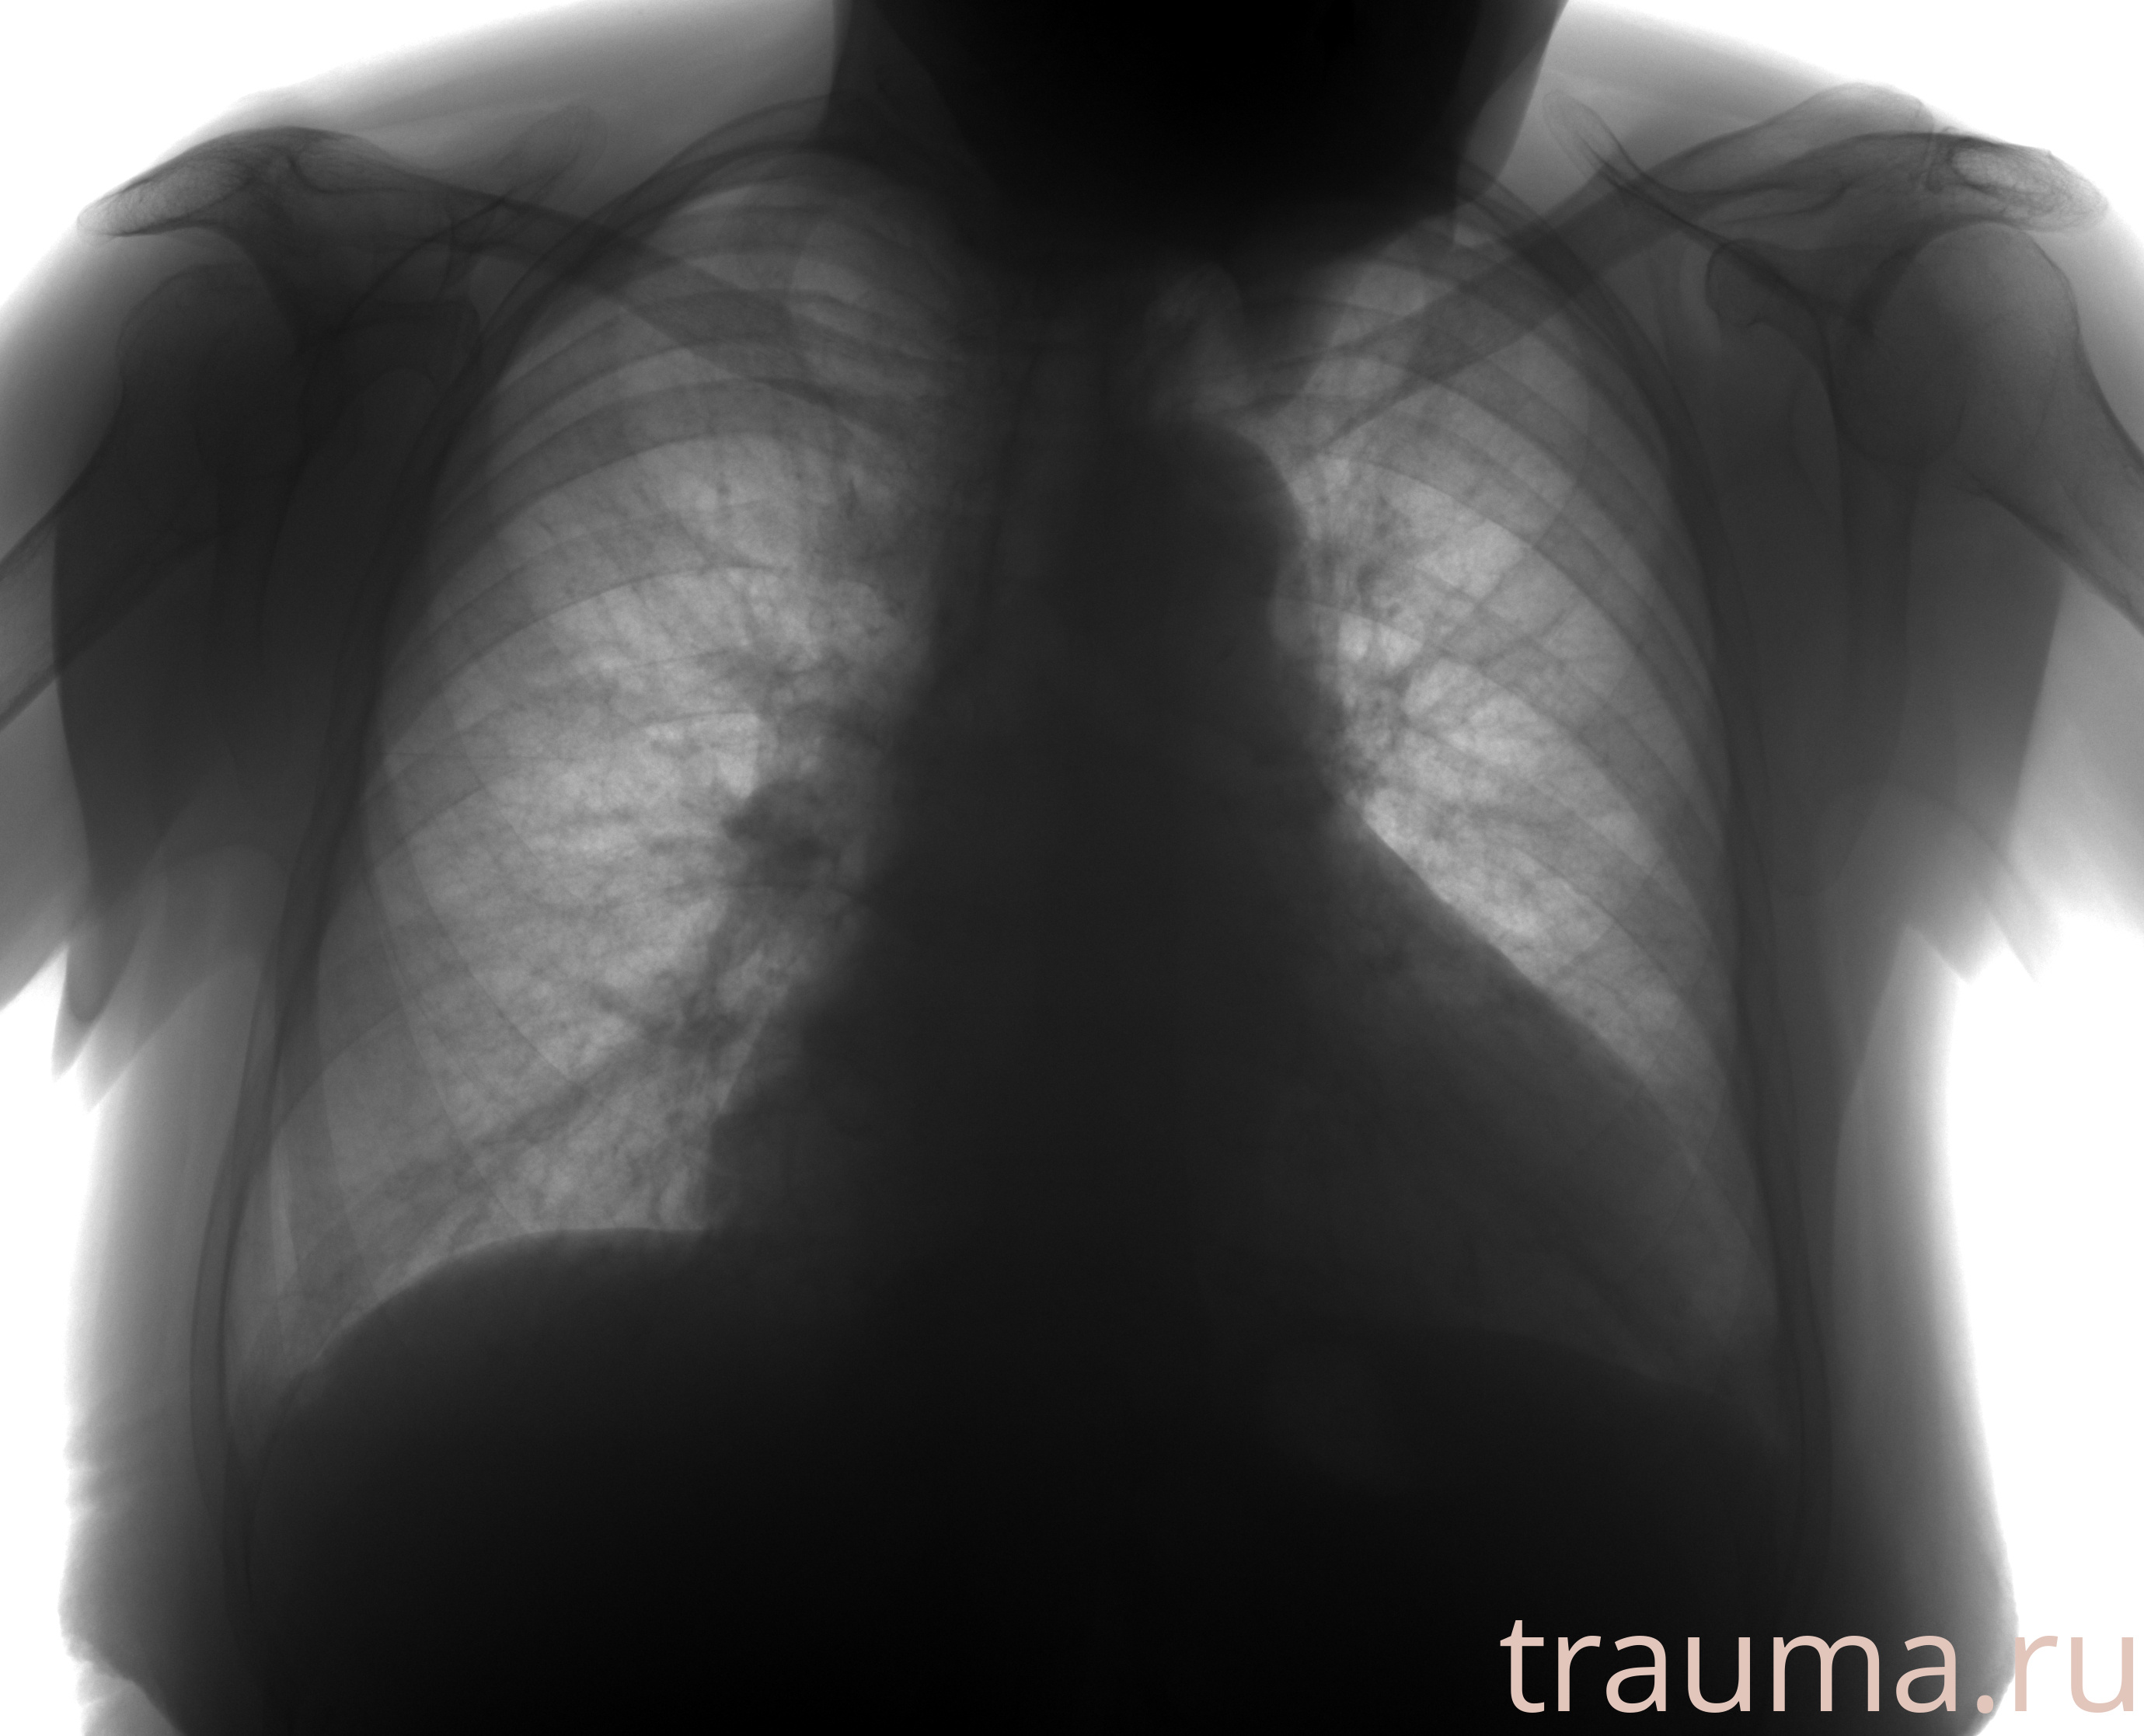

Рентгенограммы

Рентген на дому: по вашему адресу приезжает врач-рентгенолог, травматолог-ортопед с мобильным рентгеновским аппаратом, проводит диагностику травмы или заболевания, делает необходимые рентгенограммы, дает рекомендации по дальнейшему лечению. Получить качественные снимки в домашних условиях возможно благодаря уникальной методике, разработанной МосРентген Центром для института  Склифосовского